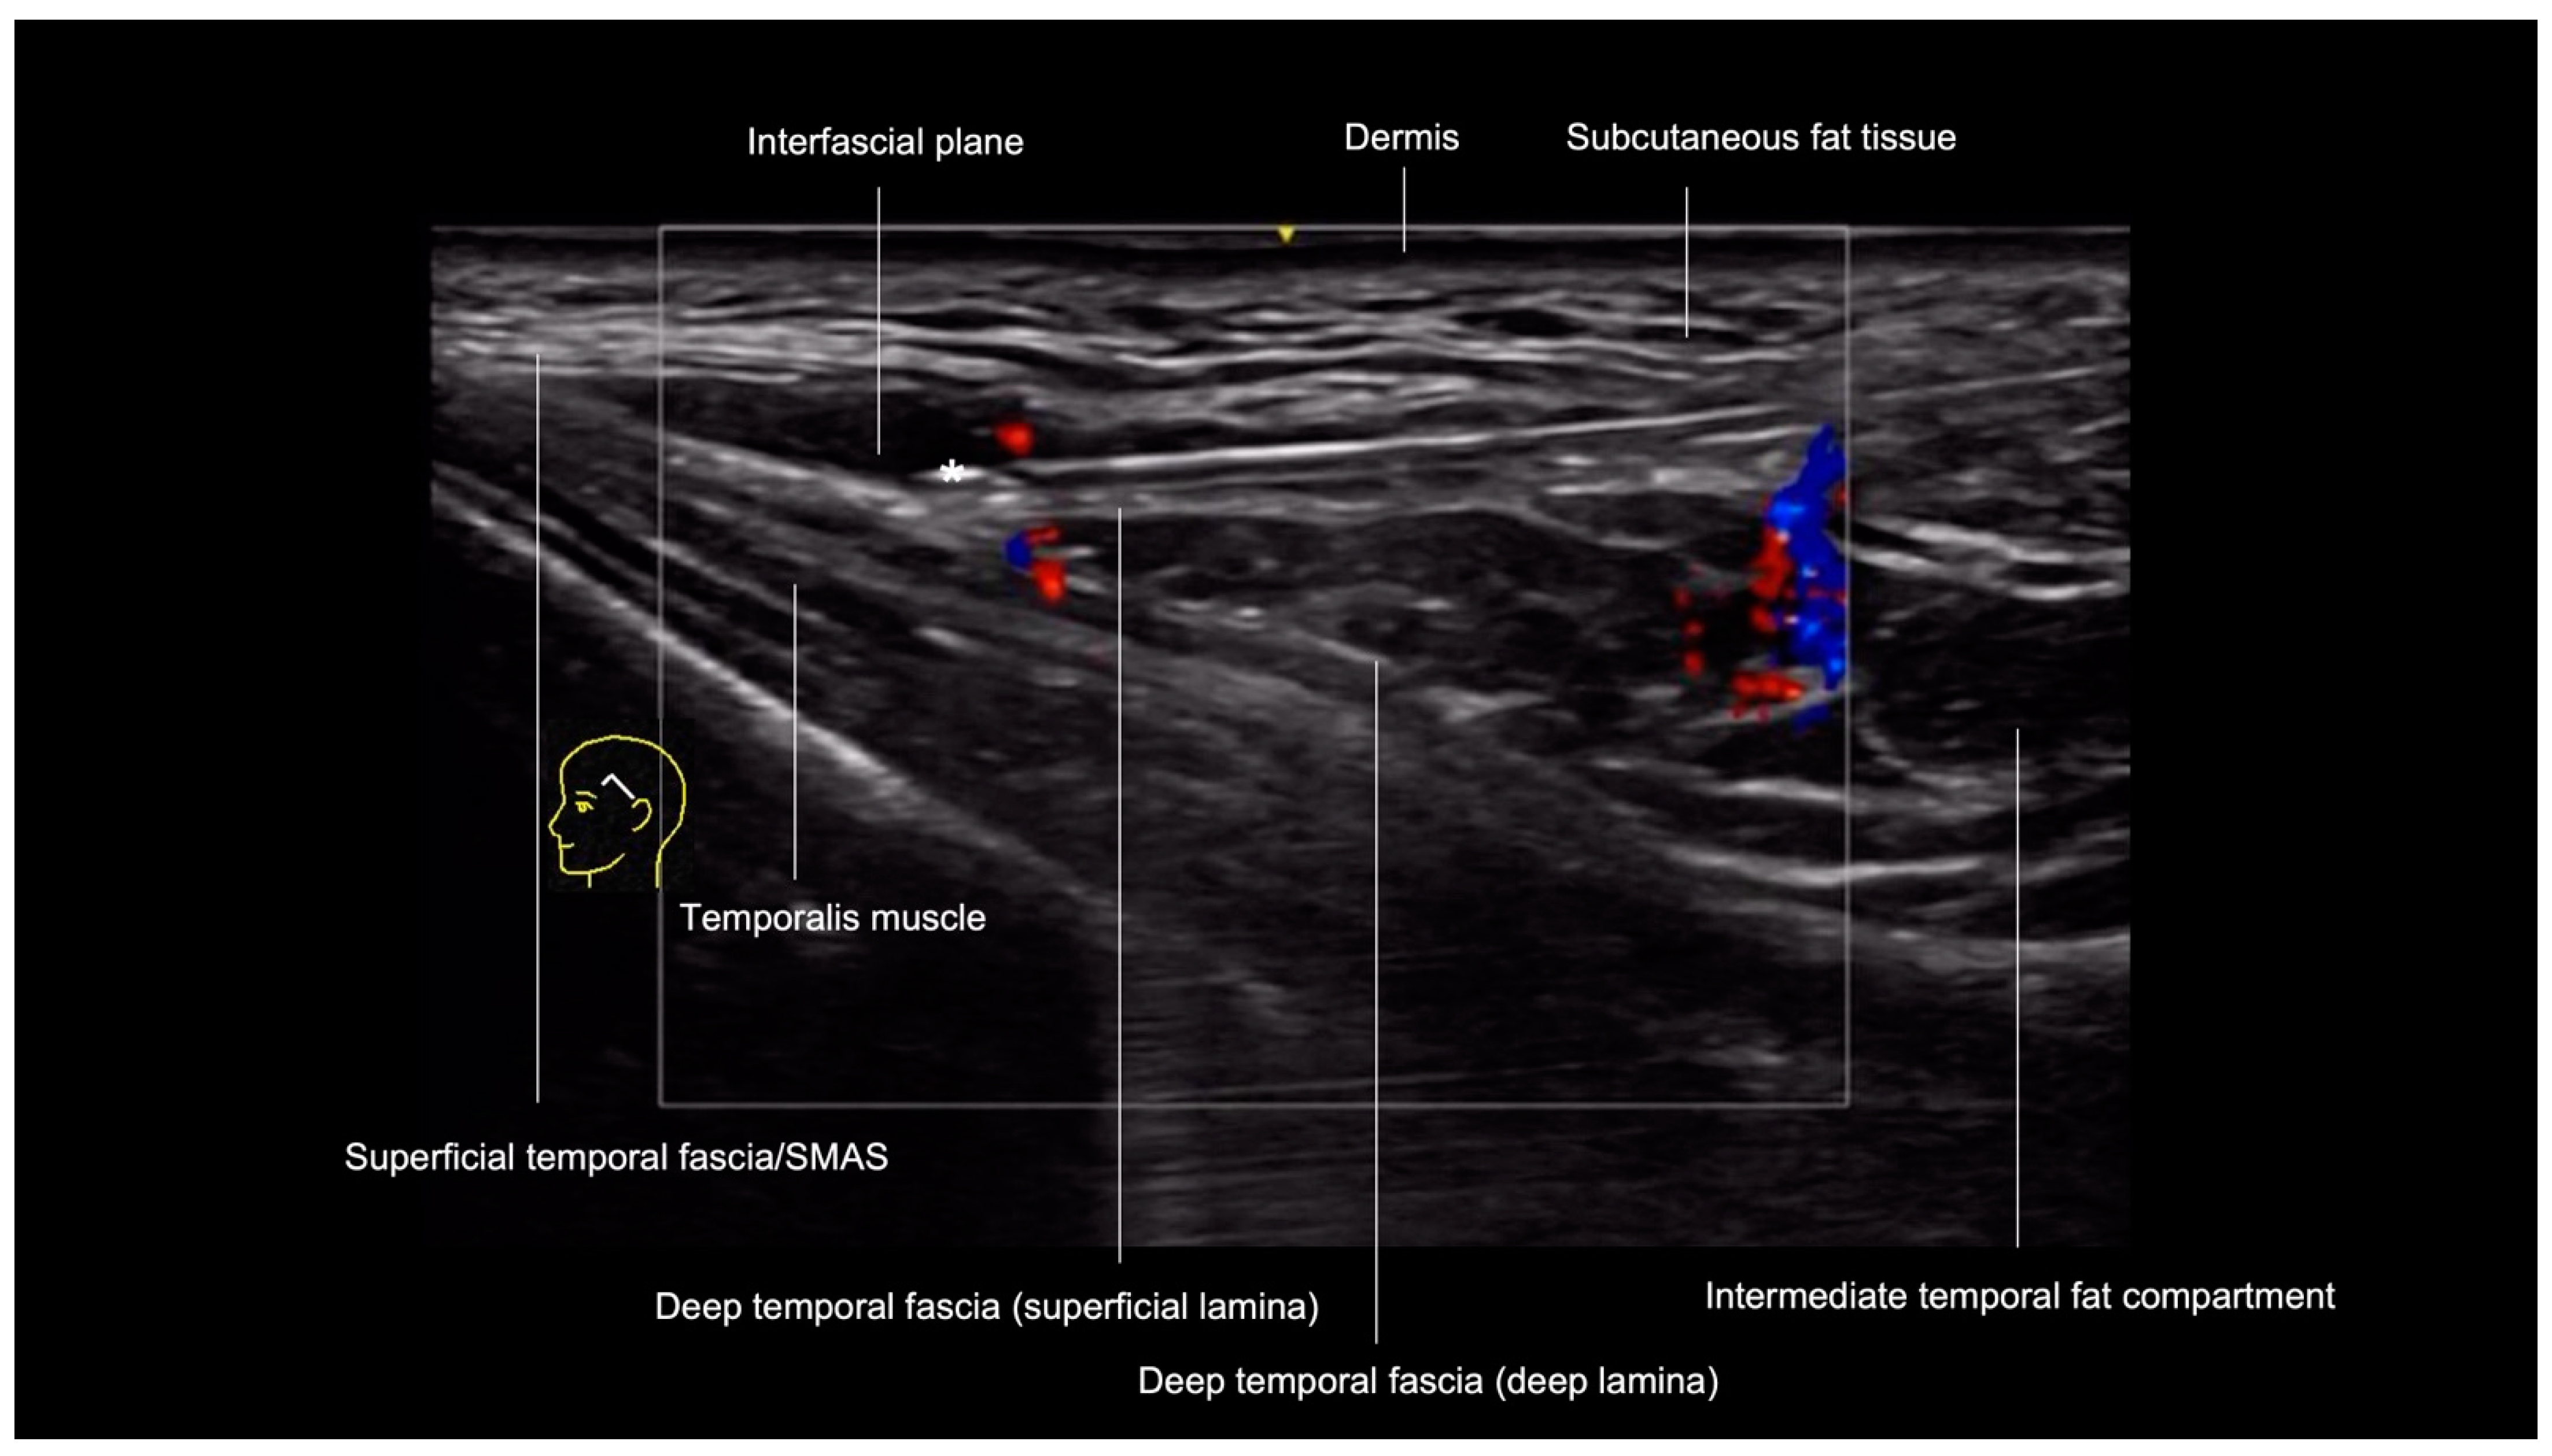

- Technique 2: Interfascial filler placement

| Temporal Region Technique 2: Interfascial filler placement | No | Yes | Interfascial plane between the superficial temporal fascia and deep temporal fascia (superficial lamina) | Superficial temporal artery and vein, middle temporal vein, sentinel vein |